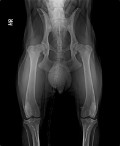

Selbstverständlich beziehe ich dabei vorliegende tierärztliche Diagnosen, Röntgenbilder, Arztberichte und andere

Untersuchungsergebnisse mit ein.